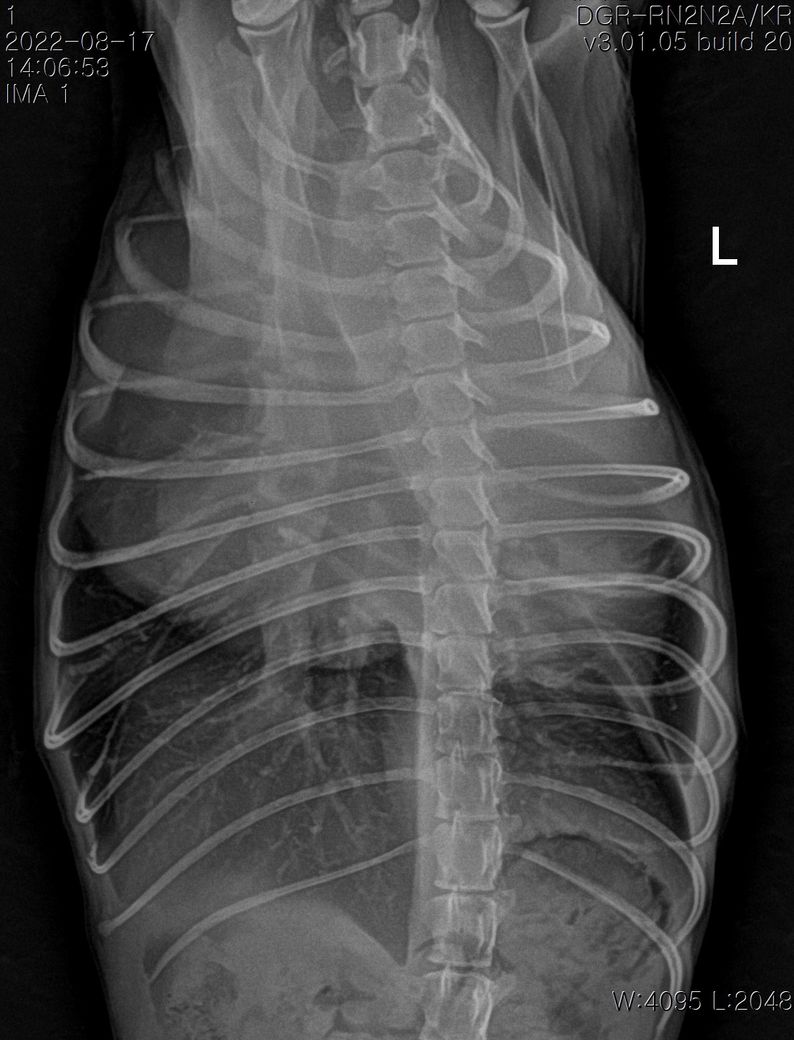

폐에 종양의심소견이 보인다고 해서요.

7월부터 기침을 간헐적으로 하다가 최근 심해져서 병원에 갔는데 엑스레이 상 폐종양이 의심된다고 해서요.

첨부해주신 사진만을 기초로 볼때 폐종양인 경우 좌측 폐전엽부의 종양이, 폐종양이 아닌 경우 종격동내의 종양 특히 흉선종양의 가능성이 높아 보입니다.

이 두가지 종양의 가능성이 사실 가장 높은 상태에서 CT 촬영을 해보아야 하는 이유는

폐종양의 경우 수술로 적출하는것이 비교적 수월하고 수술 이후 어느 정도 절제 하느냐에 따라 정상 생활까지 가능한 상태가 될 수 있기 때문입니다.

물론 폐 종양이 좌측 폐 전엽의 앞쪽 부분에 국한하여 있을 때만을 이야기 하는것으로

만약 좌측 폐전엽의 뒤쪽 부분까지 적출해야 하는 상태의 종양인 경우 수술 이후 호흡 부전이 잘 오고 산소처치를 계속 받으면서 살아야 할 가능성도 고려해야 합니다.

좌측 폐는 산소 교환 능력의 40% 정도를 차지하고 폐엽 절제술 후 산소 교환능에 영향을 주는 기준점이 40% 폐엽이니까요.

앞으로의 처치 방향을 결정하기 위해서라도 CT 촬영을 통해 수술 가능종양인지, 수술을 하지 않더라도 다른 중재적 시술이나 내과적 치료의 플랜을 짜야 하는 상황이라고 보시면됩니다.